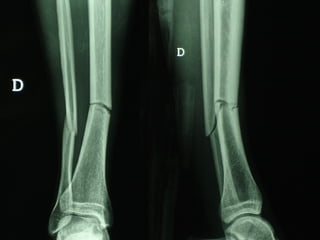

Dal Gennaio 2000 al Febbraio 2006 abbiamo trattato 167 fratture chiuse  con placca percutanea  in 164 pazienti :  27 lesioni diafisarie di gamba, 12 piloni tibiali ,  11 fratture prossimali di tibia, 36 fratture sovracondiloidee di femore, 17 fratture diafisarie di femore, 43 fratture metaepifisarie prossimali di omero, 21 diafisarie d’omero.  156 guarigioni 8 fallimenti

Dal Giugno 2002 al Dicembre 2004 abbiamo trattato 5 fratture esposte: 3 di tibia e 2 di ulna 5 guarigioni

I buoni risultati ottenuti dipendono da 5 punti fondamentali:   una accurata riduzione percutanea della frattura  precise vie di accesso  l’utilizzo della placca che consenta il più lungo braccio di leva possibile il pretensionamento della placca  una sintesi con un ridotto numero di viti

Fratture  esposte